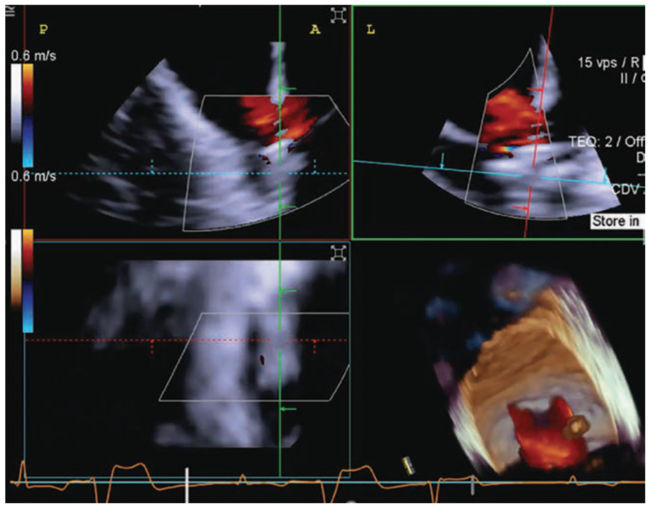

Transesophageal echocardiography (TEE) is considered the gold standard for image guidance during tricuspid valve repair. However, the ability to position the TEE ultrasound probe is limited by the esophageal path, the distance to the tricuspid valve, and challenging transgastric en-face views. Four-dimensional intracardiac echocardiography (4D ICE) overcomes TEE’s limitations and provides unobstructed adjacent views of the tricuspid valve and leaflet anatomy. In this case, a patient with severe tricuspid regurgitation (Figure 1) presented for tricuspid transcatheter edge-to-edge repair (TEER). The use of TEE with an ICE catheter (the ACUSON AcuNav Volume ICE catheter, Siemens Healthineers) provided detailed views of tricuspid leaflet anatomy (Figure 2), enabling accurate deployment of a leaflet approximation device. Following TEER, tricuspid regurgitation was significantly reduced (Figure 3) and the patient reported symptomatic improvement.